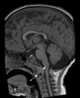

Hypoplasia of dens

Hypoplasia of dens is a congenital non-formation of the pivot point of the second cervical vertebra, which leads to spinal cord damage. Onset of the condition may occur at any age, producing signs ranging from neck pain to quadriplegia. [Source: Wikipedia ]